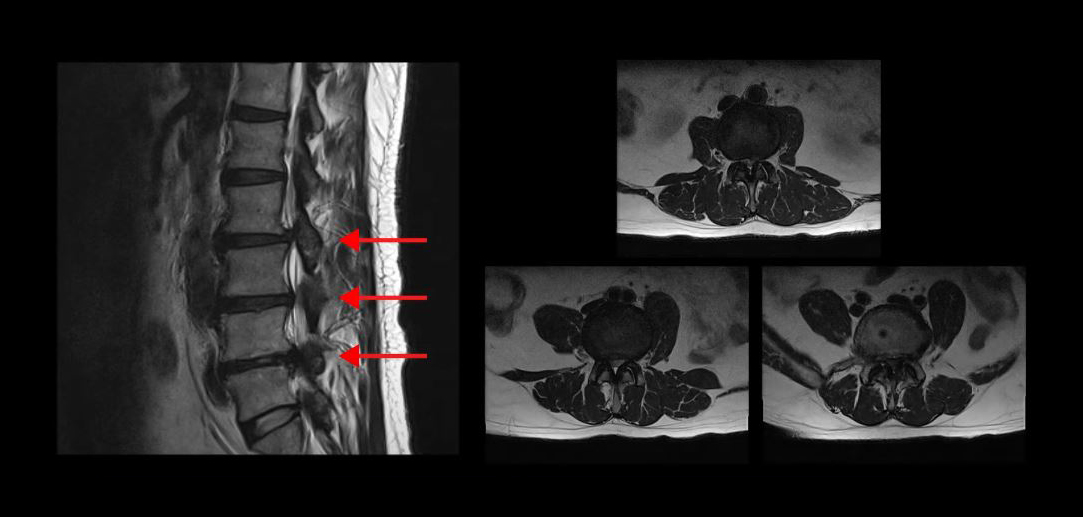

먼저 첫 번째 케이스의 환자분입니다.

이 환자분의 MRI를 보시면 무려 세 마디의 척추관이 심하게 막혀있어서 거의 걷지 못하는 분입니다. 무려 25년간 허리통증과 협착증 증상으로 고생하셨습니다. 그런데 서울 최상급 대학병원에서는 여러 마디가 안 좋으니 매우 어려운 수술이고 수술의 실익이 없다고 그냥 참고 살라는 말을 들으셨고, 서울 유명 척추전문병원에서는 세 마디를 한번에 수술하면 견디기 어려우니까 3주에 걸쳐 세 번의 수술을 하자는 말을 들으셨습니다.